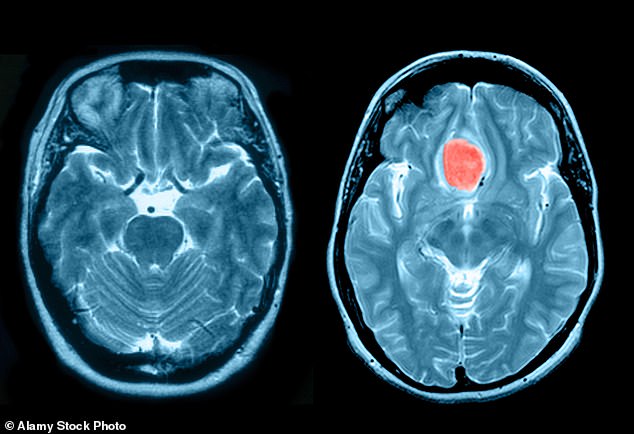

Meningioma is the most common type of brain tumour, and is most found in women

Although non–cancerous, the condition can cause blurred vision, headaches, hearing loss, poor sense of smell and problems with swallowing. Tumours are normally slow–growing but can kill by compressing the brain and nerves if they grow too big.

Between 2,000 and 3,000 people a year in the UK are diagnosed with a meningioma and it’s more common in women.